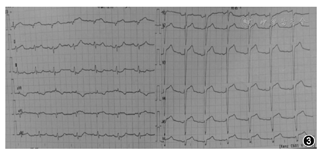

患者男,63岁。因"突发胸痛2 h"入院。患者晨起活动时突发剑突下压榨性疼痛,持续不缓解,伴全身大汗淋漓,无其他部位放射痛,无头痛、晕厥,无咳嗽、咯血,无恶心、呕吐,无呼吸困难。既往有高血压病史10余年,糖尿病病史3年。入院体检:体温36.5℃,脉搏63次/min,呼吸17次/min,血压118/76 mmHg(1 mmHg=0.133 kPa)。神志清,精神稍萎靡,痛苦面容,心肺腹体检未见明显异常。急诊查心电图示:窦性心律;V1~V4导联R波递增不足;V5、V6导联ST段上斜型压低伴有J点下移;V2~V4导联T波高尖;aVR导联ST段稍抬高(图1);肌钙蛋白I<0.10 μg/L、肌酸激酶同工酶<2.00 μg/L、肌红蛋白<20.00 μg/L;D-二聚体0.16 mg/L;N末端B型利钠肽前体4 560 ng/L。考虑de Winter综合征,拟诊"急性冠状动脉综合征(ACS)"收入冠心病重症监护室(CCU),予阿司匹林300 mg、替格瑞洛180 mg口服后行冠状动脉造影(CAG)示:开口正常,左冠状动脉主干(LM)未见明显狭窄;左冠状动脉前降支(LAD)近段闭塞,前向血流心肌梗死溶栓治疗(TIMI)0级(图2A);左回旋支(LCX)正常,前向血流TIMI 3级;右冠状动脉(RCA)中段斑块,前向血流TIMI 3级;于LAD病变处行经皮冠状动脉介入(PCI)治疗,置入支架一枚,术后LAD血流恢复,前向TIMI 3级(图2B)。术后约2h复查心电图提示:窦性心律,V4~V6导联下压的ST段恢复至基线附近,V2~V5导联高尖T波变低,aVR导联ST段也恢复至正常水平(图3)。

1947年,Dressler和Roesler[1]通过分析急性心肌梗死(AMI)的早期心电图表现,发现部分AMI患者的心电图合并存在ST段上斜型压低,但未进一步研究。直到2008年,荷兰医生de Winter等[2]对所在医院1 532例前降支近端闭塞患者的心电图特征进行回顾分析,发现约占2%的患者并没有典型的心肌梗死心电图改变,并将这种新的高度提示ACS的心电图表现命名为de Winter综合征。这些不典型心电图常表现为[2]:(1)胸前V1~V6导联ST段在J点后呈上斜型压低1~3 mm,并和直立高尖对称的T波相延续;(2)胸前导联T波高尖对称;(3)QRS波群一般不增宽,或者仅有轻微增宽;(4)少数患者可存在胸前导联的R波递增不良;(5)在大多数患者,aVR导联ST段抬高1~2 mm。本例患者心电图提示V4~V6导联ST段上斜型压低,V2~V5导联T波高尖,aVR导联ST段稍抬高。符合上述(1)(2)(5)3点,因此被诊断为de Winter综合征。